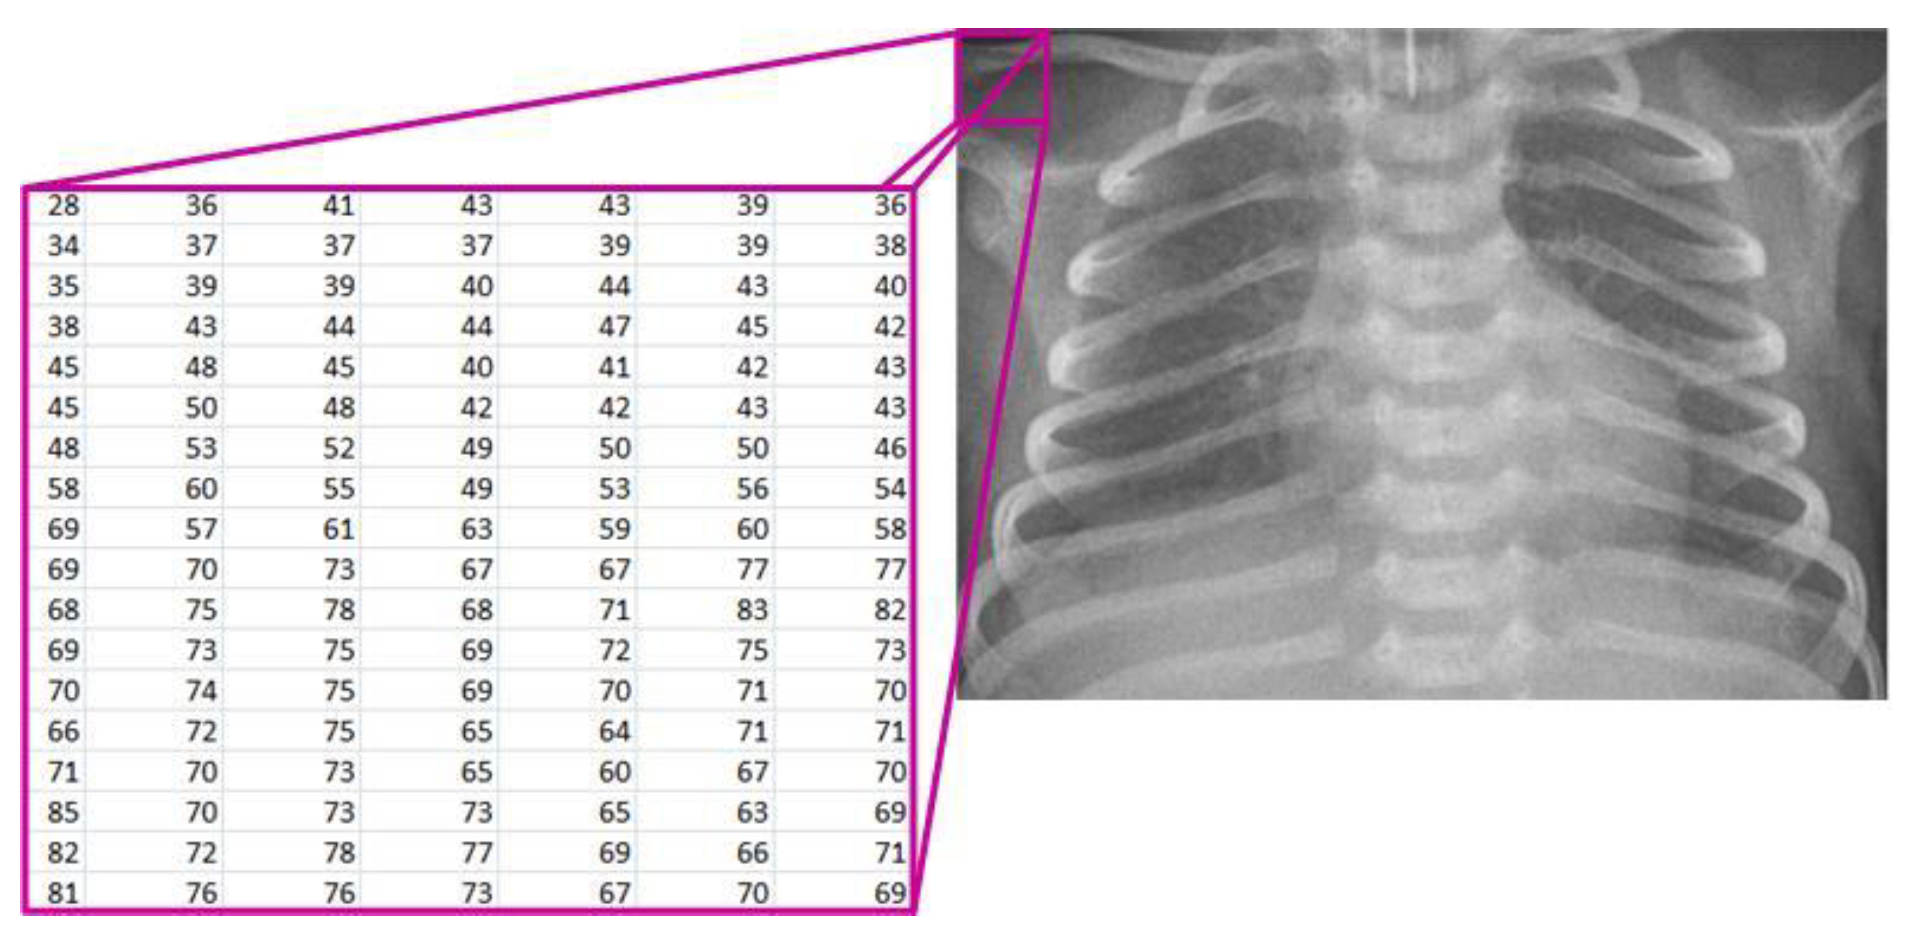

Starting from the image loaded from the corresponding database, it is displayed on the screen and treated mathematically (Figure 2). The image is denoted as [7,19]:

X R M x N ,   w h e r e   X i ,   j 0 ,   255   f o r   i = 1 ,   2 , ,   M   a n d   j = 1 ,   2 ,   ,   N ,

where

• R—the set of real numbers;

• M—the number of rows in the image;

• N—the number of columns in the image;

• X(i, j)—the pixel intensity at position (i, j).

Figure 2. Mathematical representation of the X-ray image.